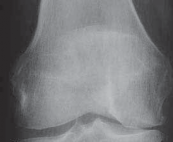

FIG 2 • A. AP radiograph of the right knee showing significant narrowing of the medial joint space with flattening of the medial femoral condyle and osteo-phyte formation. B. PA 45-degree flexed view (ie, Rosenberg view) of the same knee is obtained to show a different tangential view of the condyles. In this view, the patient has cartilage space remaining, but the medial compartment is narrowed. The numbers written in the condyles represent millimeters of joint space. C. Mechanical axis view of the bilateral lower extremities shows severe bilateral varus deformities of the lower extremity. Although the picture is underpenetrated toward the femoral heads, the steps for obtaining the mechanical axis are as follows: (1) Mark the center of the femoral head. (2) Mark the center of the ankle. (3) Draw a straight line between them (ie, the most medial line on the illustration). If the line is medial to the center of

the knee, then the patient is in varus. If it is lateral,

the patient is in valgus. In this case, the patient is in severe varus.

5. Radiographic evaluation in planning for an HTO is of paramount importance. Routine radiographs to obtain include bilateral anteroposterior (AP) standing, bilateral posteroanterior (PA) 45-degree flexed (ie, skier’s view), lateral view of affected knee, and bilateral Merchant views.

1. The AP standing and PA 45-degree flexed views allow the determination and initial grading of medial or lateral joint space narrowing. Joint space narrowing often can be found at the posterior condylar area and, therefore, may be missed on a routine AP standing knee radiograph.

1. Flexing the knee to 45 degrees allows a different area of the femoral condyle to be evaluated tangentially by the xray beam and may reveal significant arthritic change (

FIG 2A,B

).